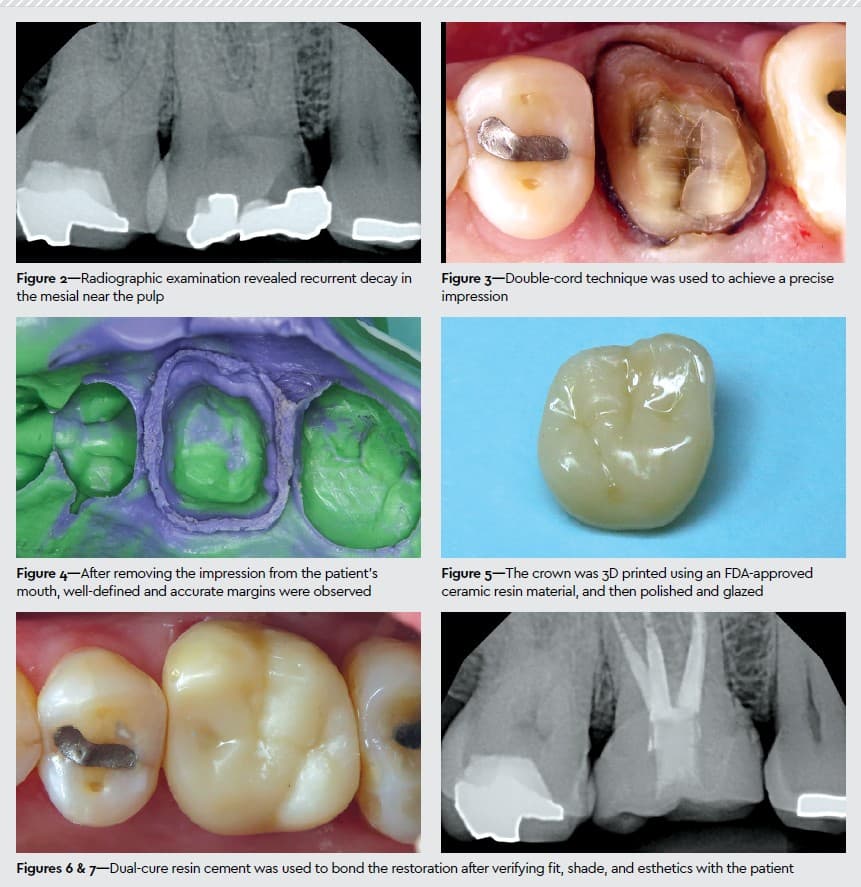

A 71-year-old man presented to our clinic with a fractured upper right first molar and cold sensitivity. A clinical examination showed an existing large MOB and OL amalgam restoration with clinical decay and fracture of the MB cusp (Figure 1). Percussion testing was negative, and cold testing was positive and lingered for 7 to 10 seconds. Radiographically, there was recurrent decay in the mesial, close to the pulp (Figure 2). Given the above findings, the diagnosis was recurrent decay, fracture, and symptomatic irreversible pulpitis. The treatment plan included caries control to determine restorability, followed by endodontic treatment and delivery of a full-coverage restoration.

We used the double-cord technique to achieve a precise impression (Figure 3). After packing both cords, retraction caps were placed over the tooth to enhance gingival retraction and promote hemostasis. A waiting period of 5 minutes was observed to allow for adequate tissue displacement. Since the distal margin was placed deeply, the PS impression technique was selected over a digital impression. The second cord was then carefully removed, and the impression was taken immediately after.

Our assistant dispensed the heavy-body impression material directly into a dual-arch, double-bite tray. While the heavy-body impression was loading on the dual-arch tray, the light-body material was injected into the gingival sulcus, around the finish line, and over the prepared tooth structure. The loaded tray was then seated onto the repared tooth area and removed 3 minutes later. After removing the impression from the patient’s mouth, we were able to see well-defined and accurate margins (Figure 4). Since the Reflection material was able to fully capture the preparation margins and emergence profile, we did not need to do a laser gingivectomy.

The dental lab poured the models, digitized the impression, designed the crown, and sent us the STL files for 3D printing in the office. We used SprintRay’s MIDAS to 3D print the crown with an FDA-approved ceramic resin material; post-processing protocols were followed to polish and glaze the restoration (Figure 5).

In the meantime, the patient received endodontic treatment on this tooth, followed by obturation of the minimally invasive access. Dual-cure resin cement was used to bond the restoration after verifying fit, shade, and esthetics with the patient (Figures 6-7). The patient left in great condition and good spirits, noting his appreciation for our efficient practice workflows and increased comfort due to the materials and technology used during treatment.